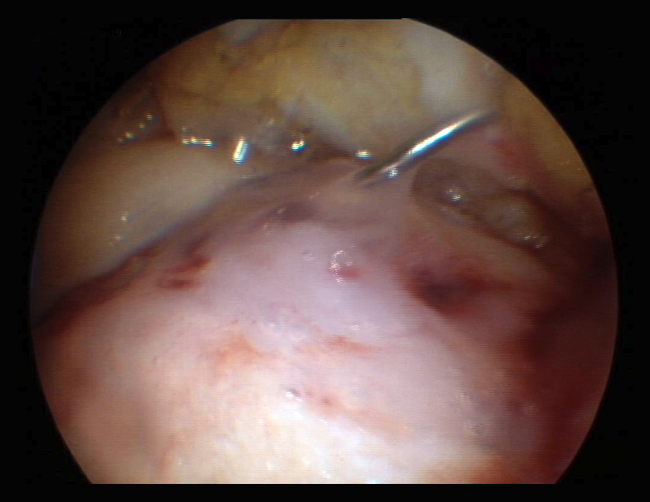

The results obtained with the microfracture techniques show variations, depending on the consulted literature source. This is due to the different hyaline characteristics of the regenerated cartilage. In some cases the percentage of fibrocartilage is high (Figure 2), due to a greater presence of type I collagen and the absence of type II collagen, in addition to the absence of a stratified cartilage tissue. Hyaline cartilage is characterized by the presence of type I collagen at the sliding surface, while type II collagen is the predominant form in the rest of the tissue, distributed to conform three basic stratification zones. These structural characteristics confer the biomechanical properties that allow long lasting function(13).

Figure 2. A: arthroscopic appearance of an ulcer with bleeding microfracture orifices; B: appearance of the same zone covered by fibrocartilage 8 months later.